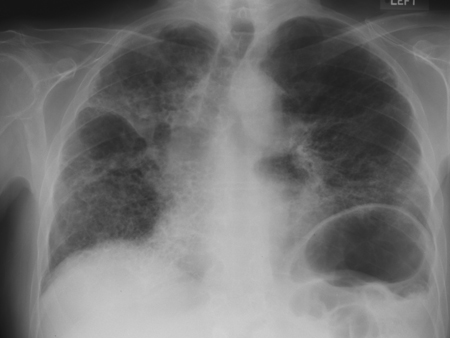

RT de enfermedad crónica por berilio

De la colección personal de Kenneth D. Rosenman, Michigan State University